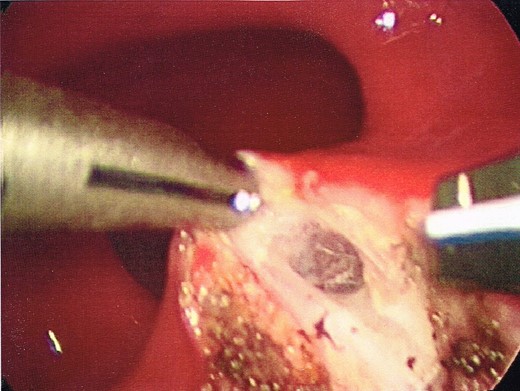

Once the dissection plane was entered, insufflation of the perirectal extraperitoneal space allowed for excellent exposure for a combination of blunt and Harmonic Scalpel dissection (Figs 4 and 5).

Enlargement of the proctotomy. The plane of dissection is visible (indicated by arrows), with the dome of the cyst seen at the bottom of the image.